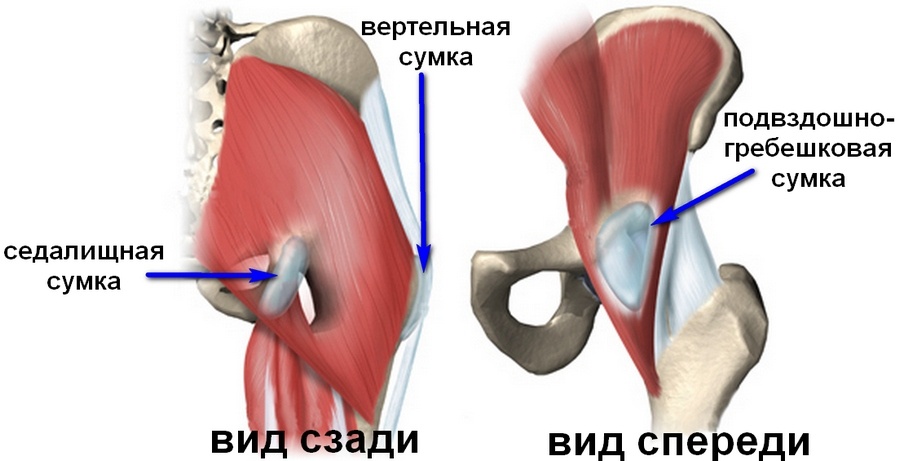

Здоровье суставов: Трохантерит и его влияние на мышцы